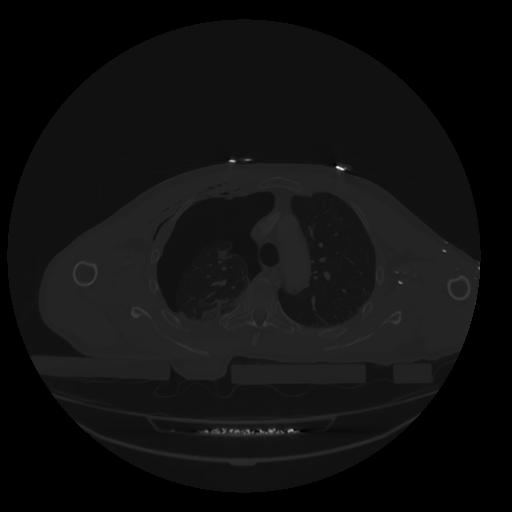

28 CUERPO,CE,Vol,2.0,CUERPO,,